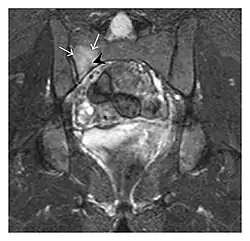

Figure 1: A 56-year-old woman presenting with left knee pain after a fall. (a) Initial anteroposterior radiograph was considered normal, however, subtle cortical disruption of the anterior rim of the medial tibial plateau, medial to the tibial spine, is noted (arrow). (b) Coronal T1-weighted MRI confirms the cortical disruption (arrow) and shows extensive fracture through the proximal tibia. (c) Coronal proton density-weighted image with fat saturation shows extensive edema in the subchondral bone. Note also hypersignal adjacent to the medial collateral ligament corresponding to a grade I sprain (arrowheads).[1]

Figure 13: Partial osseous avulsion of the gluteal muscles at the greater trochanter in a 59-year-old man who presented with the right hip pain without a history of trauma. Lauenstein view and anteroposterior and radiographs (not shown) did not show an obvious fracture line or disruption of bony contours in the acetabulum or the right femoral neck. (a) Coronal T1-weighted MRI displays an incomplete fracture line extending partially from the greater trochanter (arrow). (b) Coronal short tau inversion recovery MRI shows heterogeneous hyperintensity in the same region (arrow) as well as hyperintensity within the gluteus medius and minimus muscles (arrowheads) consistent with tissue edema and hematoma.[1]

Figure 14: Subcapital insufficiency fracture in a 55-year-old man with a left hip pain without a history of trauma. Anteroposterior and Lauenstein view radiographs centered on the left hip do not show an obvious fracture line, but mild acetabular osteophytosis was noted consistent with hip osteoarthritis (not shown). (a) Coronal T1-weighted MRI shows a linear low-signal band through the femoral neck corresponding to a fracture line (arrowheads). (b) Bone scintigraphy shows focal uptake (arrow) corresponding to the fracture.[1]